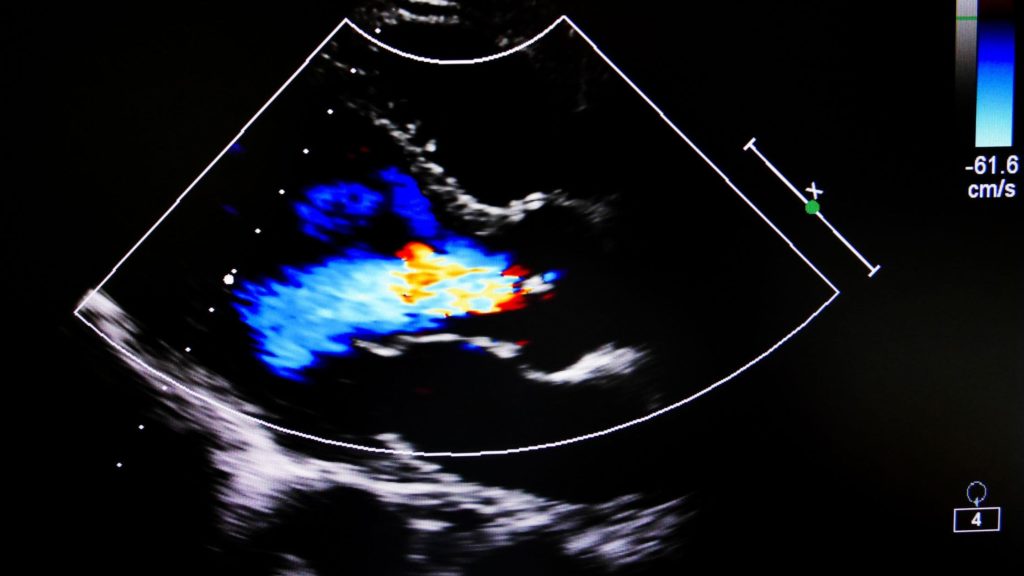

Color Doppler Imaging

With this imaging mode, users can visualize and analyze the flow of blood, its direction, and vascularization. Color Doppler Imaging is often used in cardiology to help analyze heart conditions.